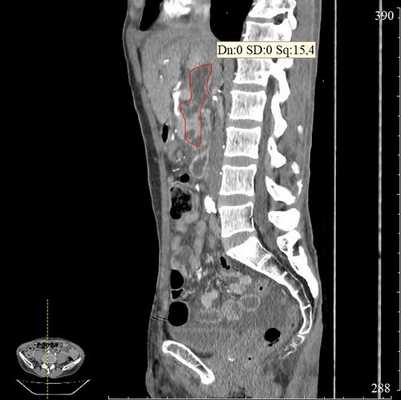

КТ органов брюшной полости. Псевдокиста поджелудочной железы у пациента после приступа острого панкреатита

1. Проведение в желудок эхоэндоскопа OlympusGF-UE 160 и эндоскопическое ультразвуковое сканирование органов брюшной полости для определения зоны контакта стенки кисты со стенкой желудка (рис. 1). Рис. 1. Эхоэндоскопия и ультразвуковая визуализация панкреатической псевдокисты в теле поджелудочной железы (случай 1).